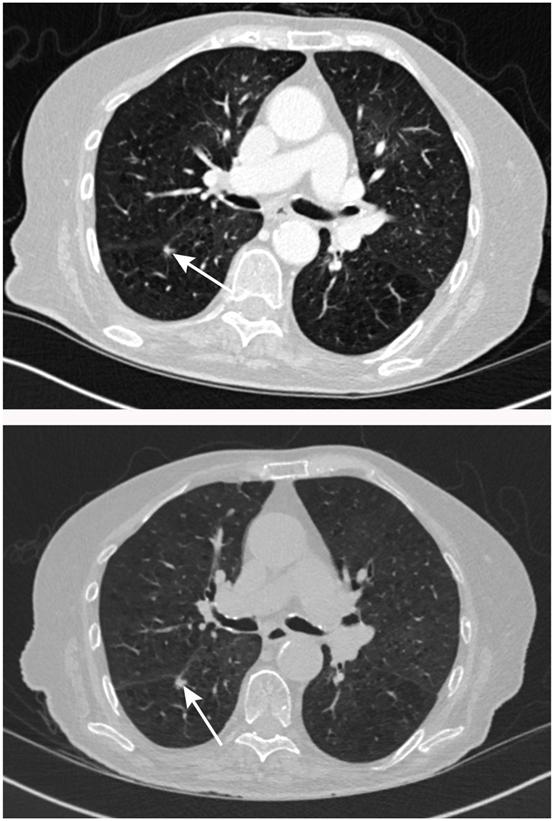

当结节大小介于两者之间(直径5-8 mm或体积80-300 mm3)时,则需要通过CT监测评估结节的恶性风险。具体流程见下图。

直径≥6 mm或体积≥80 mm3的实性结节患者,需要在基线评估3个月后复查CT,如体积倍增时间(VDT)<400天或发现结节增长的明确证据,则需要采取进一步措施明确结节性质。

对于直径5-6mm的实性结节患者,一般在基线评估1年后复查CT,根据结节大小变化或VDT决定后续处理方式。

结节体积稳定的患者无需后续处理,而结节直径稳定的患者需要在基线评估2年后复查CT,如结节大小稳定可停止CT监测。具体流程见下图。

直径<5 mm或4年间大小稳定的亚实性结节患者无需后续处理,相反则需要每3个月复查胸部CT评估结节变化。

如结节大小稳定,需要进一步利用Brock模型评估结节的恶性风险,并且根据结节形态变化以及患者意愿决定后续处理方法。

如结节增长或形态发生变化(如新出现实性成分),则考虑外科手术切除或非手术治疗。具体流程见下图。